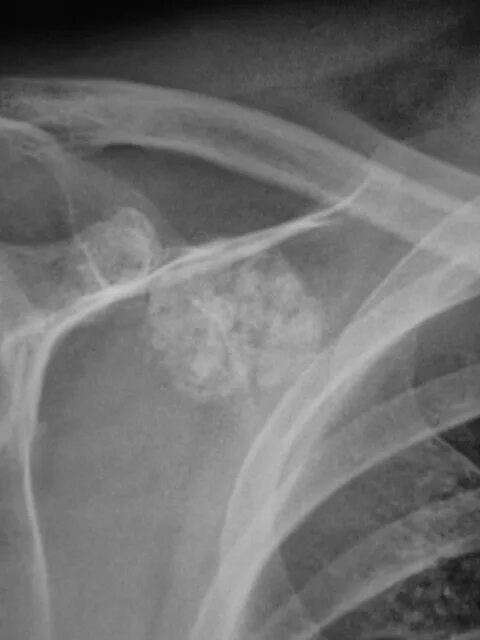

Метастазы в ключице